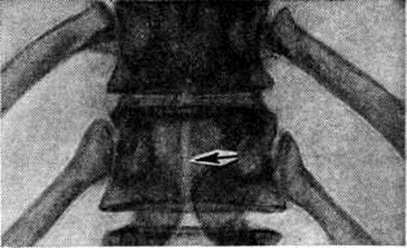

Локализация расщелины в теле или дуге позвонка может быть самой различной (рисунок 2). Рентгенологически легче распознаются расщелины, ориентированные в сагиттальной плоскости, которые лучше видны на рентгенограмме в прямой проекции. Расщелины в боковых отделах дуг и тел видны на рентгенограммах в боковой проекции, а иногда только на томограммах. При локализации в телах позвонков (spina bifida anterior) щель делит тело позвонка на две части, каждая из которых имеет на рентгенограмме в прямой проекции клиновидную форму. Чаще обе части тела позвонка расположены симметрично, напоминают по виду крылья бабочки — так называемый бабочковидный позвонок. Однако клиновидные части тела позвонка могут быть и асимметричными (рисунок 3). В процессе роста тела соседних позвонков приспосабливаются к форме аномальных позвонков.

Чаще встречаются дефекты в дугах позвонков, особенно нижних поясничных и крестцовых. Наиболее типично незаращение дуги по средней линии с расщеплением и недоразвитием, а иногда и отсутствием остистого отростка. Эта локализация Спина бифида легко выявляется на рентгенограмме в прямой проекции (рисунок 4). Реже расщелина локализуется в дуге между суставными отростками с одной или с обеих сторон — спондилолиз (рисунок 5). Диагностика Спина бифида этой локализации сложна, если она не сочетается со спондилолистезом (смотри полный свод знаний). При подозрении на спондилолиз обязательна рентгенография в двух проекциях, а при недостаточной информативности рентгенограмм необходимо томографическое исследование в боковой проекции (смотри полный свод знаний: Томография).